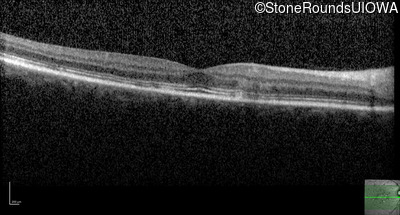

Optical Coherence Tomography - Left - 20/20 -3

Exemplar / OCT Stack

OCT Stack